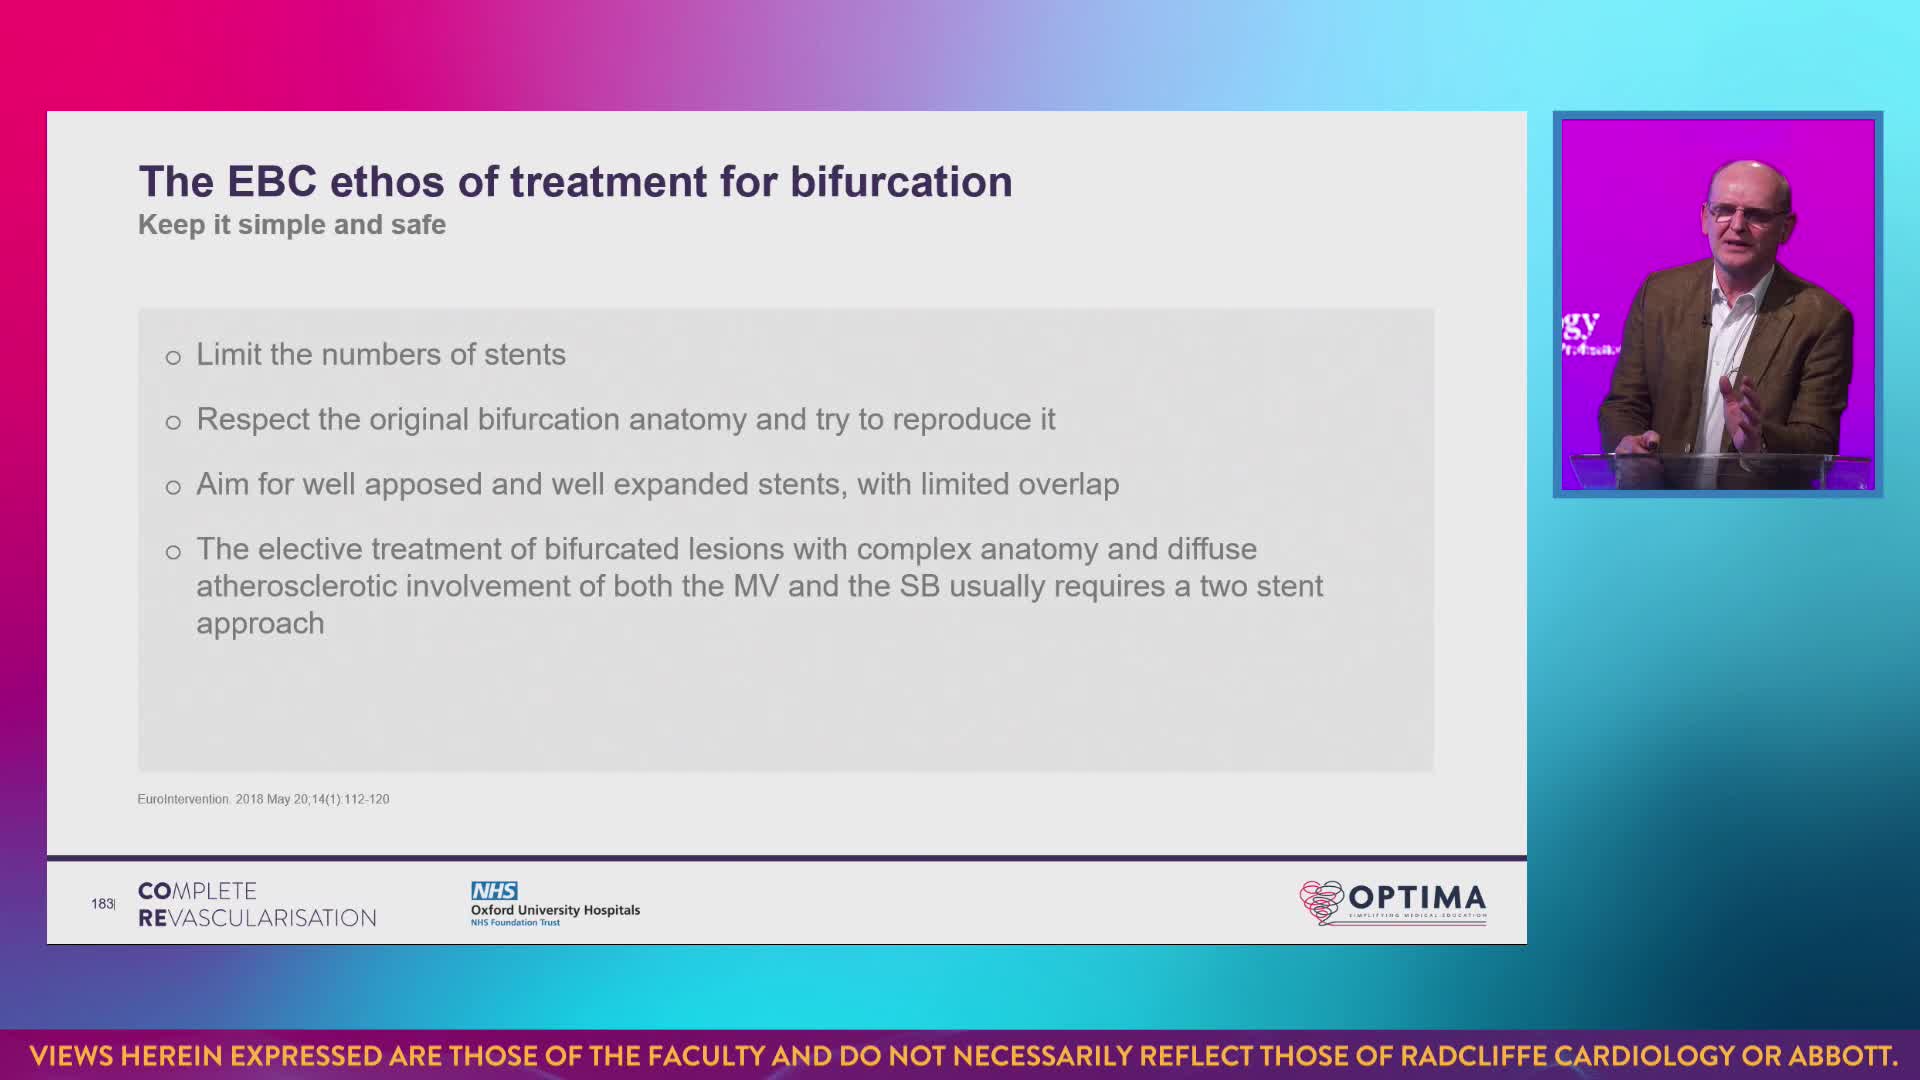

The integrated use of physiology and imaging is transforming the treatment of complex bifurcation disease. We explore...